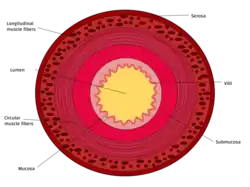

The three sections of the small intestine look similar to each other at a microscopic level, but there are some important differences. The parts of the intestine are as follows:

This cross section diagram shows the 4 layers of the small intestine wall.

Layer Duodenum Jejunum Ileum

Serosa 1st part serosa, 2nd–4th adventitia Normal Normal

Muscularis externa Longitudinal and circular layers, with Auerbach's (myenteric) plexus in between Same as duodenum Same as duodenum

Submucosa Brunner's glands and Meissner's (submucosal) plexus No BG No BG

Mucosa: muscularis mucosae Normal Normal Normal

Mucosa: lamina propria No PP No PP Peyer's patches

Mucosa: intestinal epithelium Simple columnar. Contains goblet cells, Paneth cells Similar to duodenum, but the intestinal villus is long Similar to duodenum, but the intestinal villus is short